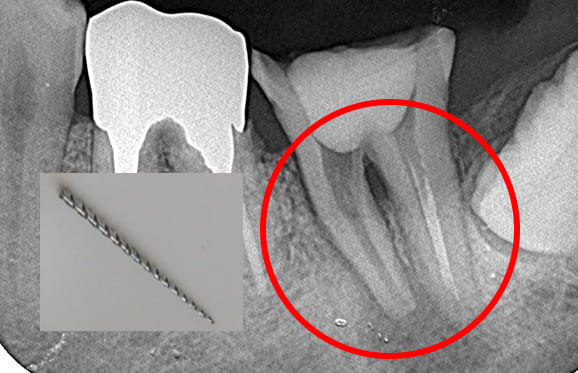

根管内の破損器具除去

● 症例1

01 左下7の近心根にエンジンファイルの破折

02 ファイル除去時

※根尖周囲の透過像はまだ残存

03 最終の根充剤を充填

※根尖透過像が小さく治癒方向へ向かっている